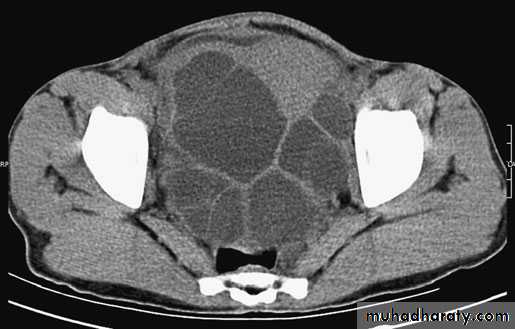

Ultrasound and CT scan are the investigations of choice. The CT scan shows a smooth space-occupying lesion with several septa .An ultrasound of the biliary tract may show abnormality in thegall bladder and bile ducts. Hydatid infestation of the biliary system should then be suspected.